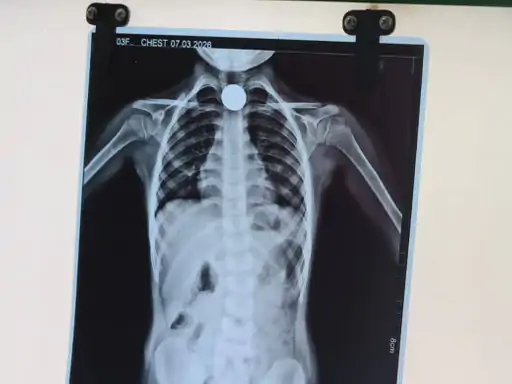

छतरपुर। जिले में एक 5 वर्षीय बच्ची के गले में फंसा 5 रुपये का सिक्का जिला अस्पताल के सर्जन डॉ. मनोज चौधरी ने बिना ऑपरेशन सफलतापूर्वक निकाल दिया। डॉक्टर की कुशलता से बच्ची को तुरंत राहत मिली और परिजनों ने भी चैन की सांस ली। यह मामला बड़ामलहरा क्षेत्र के ग्राम मैलवार का है।

अस्पताल पहुंचने पर डॉ. मनोज चौधरी ने बच्ची की जांच की। जांच में पता चला कि सिक्का उसके गले में फंसा हुआ है। डॉक्टर ने अपनी कुशलता और अनुभव का उपयोग करते हुए बिना किसी ऑपरेशन के सावधानीपूर्वक सिक्का बाहर निकाल दिया।